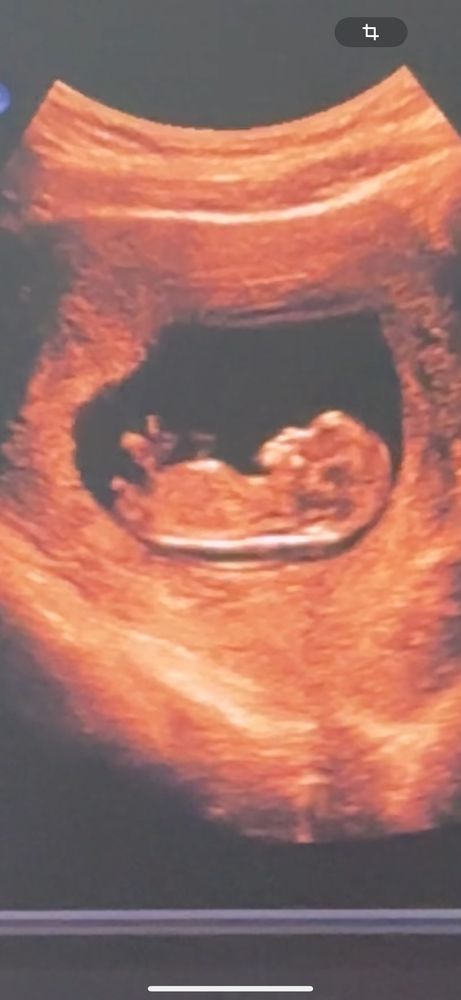

Всем хорошего настроения) Дорогие мамочки) беременные и узисты, если тут кто разбирается с полом малыша на ранних сроках беременности? Мы с мужем поспорили насчет пола ребенка)) но пока наш узист нам ничего не сказал. Срок ровно 12 нед. И еще на этом сроке нам не дали послушать сердцебиение малыша, говорят еще рано. Но я как то волнуюсь, очень хотелось послушать, так как это моя первая беременность)) За ответы заранее всем спасибо♥️

А на счет пола, в 12 недель еще не сформированы внешние половые органы..может только только супер мега эксперт узист сможет по тому как расположен бугорок определить пол. Но на этом сроке делают тест по крови матери.